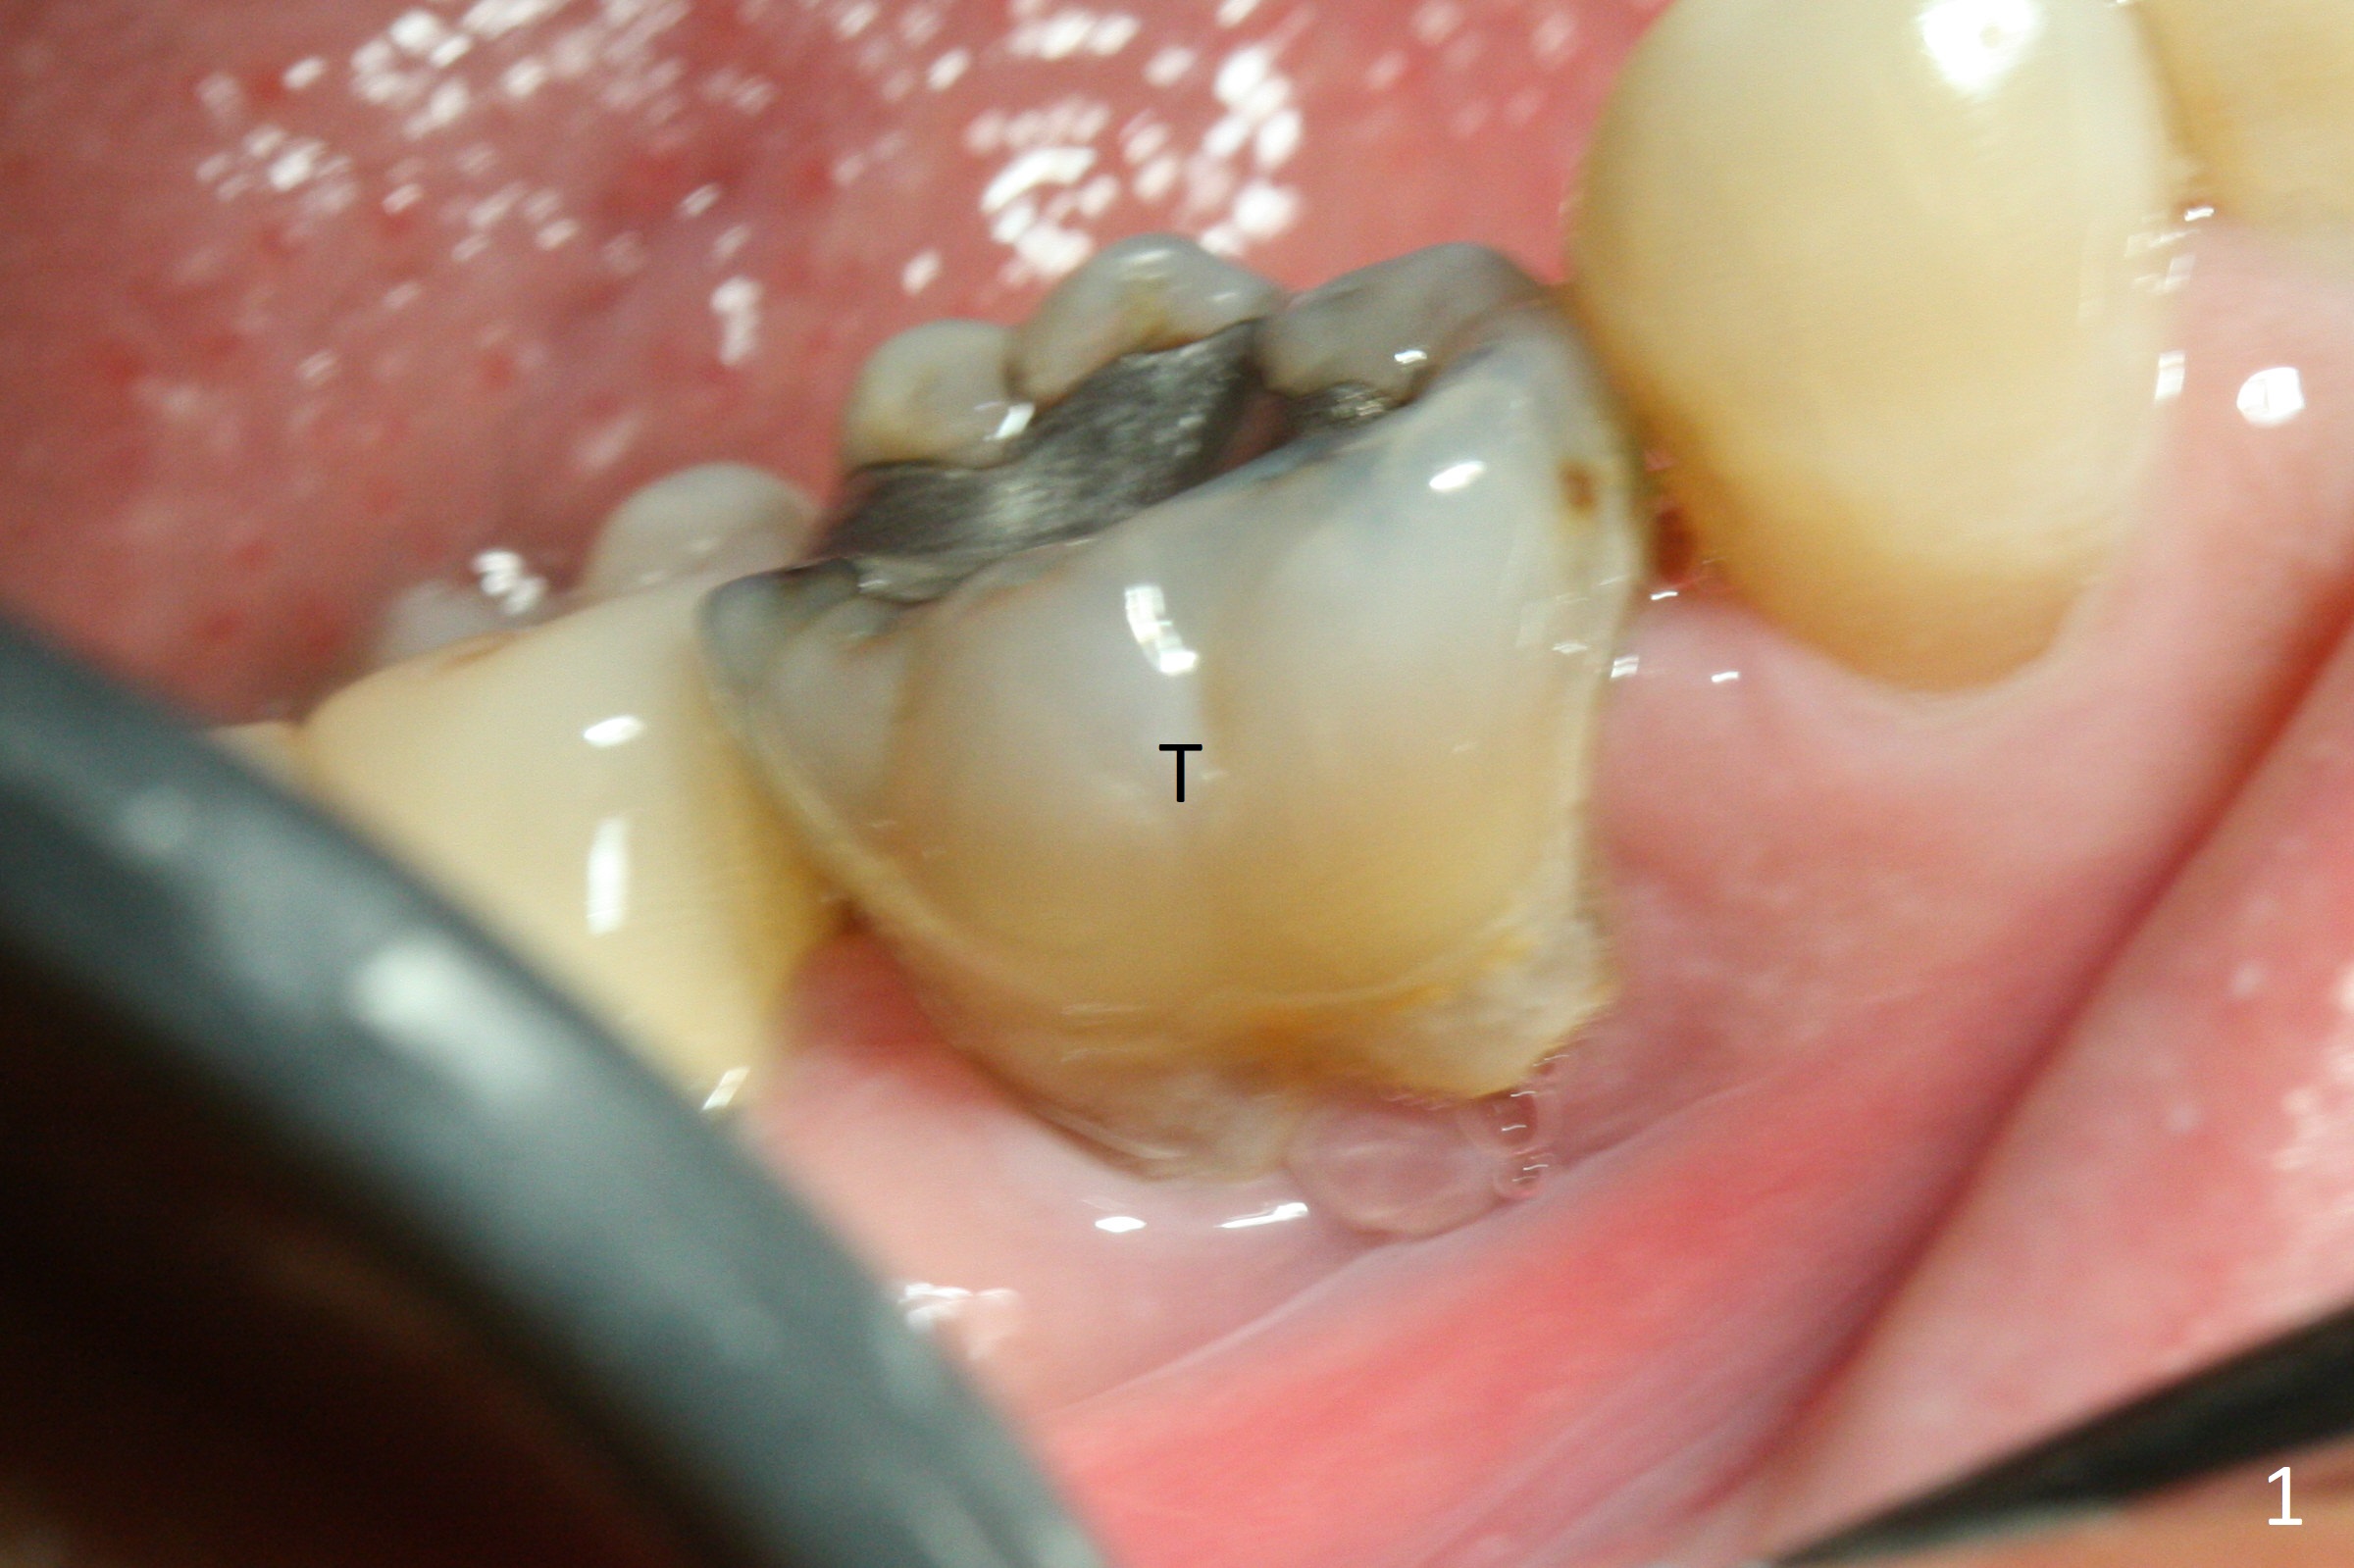

The retained deciduous tooth (lower right 2nd molar, Fig.1 T) has buccal apical infection and recession. After extraction, the initial depth of osteotomy is 11 mm over the flat socket bottom (Fig.2) without visible Mental Loop. Following 3.8 mm Magic Drill for 11 mm, a 4x11 mm dummy implant is placed partially due to hard bone; it appears that the apical osteotomy (Fig.3 yellow outline) overlaps the Mental Loop (red dashed line). For safety, a 4x9 mm IBS implant is placed with insertion torque 40 Ncm; a 5x5.7(4) mm abutment is immediately placed for an immediate provisional to cover the large socket and keep Vera graft in place (Fig.4 *). There is no postop paresthesia, probably due to the fact that the osteotomy is lingual to the Mental Loop. The provisional remains in place 7 days postop; its margin (Fig.5 arrow) covers the socket. The margin of the provisional is trimmed 1 month postop. Impression is taken nearly 3 months postop (Fig.6). The buccal plate looks atrophic 3 months postop (Fig.7 (immediately before cementation)), although there is no sign of periimplantitis. In the future, insert the immediate provisional inside of the buccal gingiva to make the buccal gingiva look bulky instead of buccal to it (Fig.5). The second drawback of placing an implant at the deciduous tooth area is that the crown is wide mesiodistally if orthodontic treatment is not rendered. Although there is lower anterior crowding, the patient declines orthodontic treatment. The bone density around the implant increases 7 months post cementation (Fig.8 *). The higher density bone seems to extend coronally 1 year 7 months post cementation (Fig.9). The dense bone apparently extends toward the abutment as well 3 years 5 months post cementation (Fig.10 curved arrows).